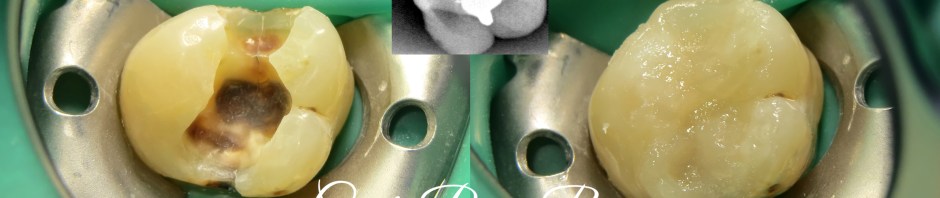

Compared with resin (4.7%) or porcelain (0.9%), the use of nonbonded inlay restoration materials such as gold (20.5%) or amalgam (18.7%) increased the occurrence of longitudinal tooth fractures (Deog-gyu Seo et al). As seen on this case, in direct restoration, amalgam gave the most effect on causing crack tooth.

Here, an upper right thid molar had been filled with amalgam for almost 5 years. The amalgam still exist but the tooth might be not. Crack lines occur from mesial to distal, adjacent to amalgam filling. The patient experienced hypersensitivity.

After taking a proper informed consent, i started treating the patient. Isolation is a must on removing amalgam. I put rubberdam (hy friedy rubberdam clamp and blossomrubberdam sheet) prior to amalgam removal. Then, i put low shrinkage stress packable composite resin, filtek bulkfill (3M) to restore the tooth. Finishing and polishing done with soflex (3M) and enhance (dentsply).

For me, xray evaluation is mandatory, i take it with Vistaray 7.1 (durr) to evaluate my restoration. It was beautifully intact to tooth structure and the body of restoration was homogeneously filled.